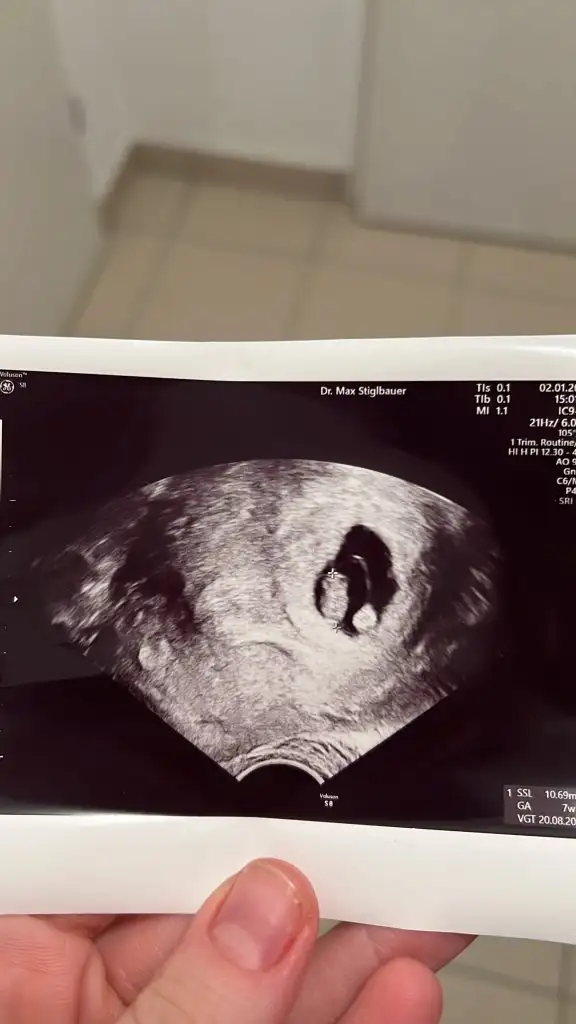

Kızlar bişey sorucam size 8. Haftadaki ultrason resmi olanlar rica etsem bir bakabilir mi? Ya da bilen varsa soldaki bebek, sağdaki yuvarlak nedir acaba? Plasenta desem daha çok erken değil mi ya da çok büyük değiş mi çözemedim ben o nedir. Ama doktor önemli bişey olsa söylerdi heralde, o anda sormadım niyezse

Yolk kesesi diyolar o mu ki acaba Erken embryo gelişiminde çok önemli olan diğer bir yapı da yolk sac dır. Bu çok damarlı yapı, besinden zengin sıvıyla çevrilidir ve plasenta görevini yapmaya başlayana kadar bu sıvıyı embryoya taşır. Aynı zamanda ilk kan hücrelerinin yapıldığı ve üreme hücrelerinin orijin aldığı yerdir.

Doğru söylüyorsun canım yolk sac galiba o bi video buldum şimdi onda da aynı bu şekilde görünüyor ultrasonu oynattıkça bi yuvarlak bi halka şeklinde içi boş görünüyor odur başka ne olucak ki..